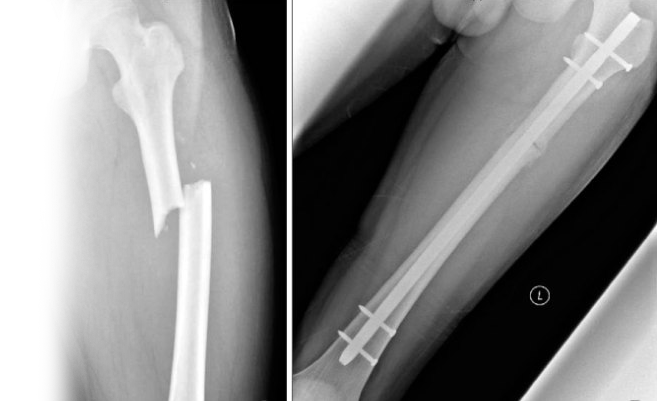

Рентгенография бедренной кости – важный метод прицельного исследования, который позволяет оценить состояние бедренной кости.

Диагностическая услуга выполняется в двух проекциях.

Рентген позволяет исключить патологию бедренной кости костно-травматического, опухолевого и воспалительного генеза.